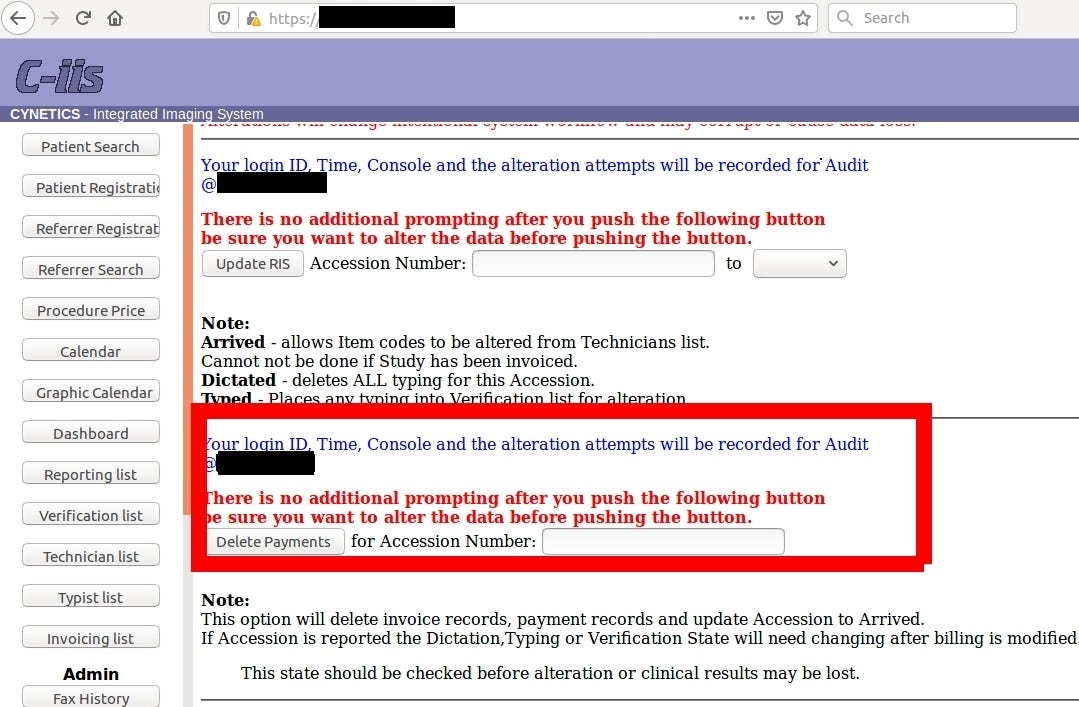

It’s worth to mention that servers was so unprotected that gave total admin rights with possibly to hijack logs and even delete patient’s payments and clinical results.

One could wreak total havoc in the server, tamper client’s data, delete payments of all patient’s or find vulnerability in Cynetics web management and penetrate the network deeper.